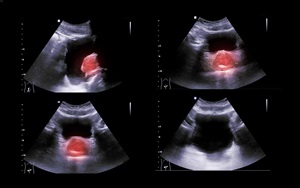

Hackensack Meridian Health offers the most advanced imaging tests for bladder cancer. Our uroradiologists are experienced in identifying tumors and the depth of any tumor invasion of the bladder and urinary tract.

Studies have shown that some forms of bladder cancer are related to a handful of genetic variants. Our uropathologists conduct molecular analysis and germline testing of your bladder cancer tissue. Through a partnership with Genomic Testing Cooperative in Irvine, Calif., a first-of-its-kind genomic profiling laboratory, we can identify your cancer’s molecular make-up and response to the immune system. The resulting genetic tumor profile allows your care team to design a unique treatment plan and identify any immunotherapies for your precise type of bladder cancer.